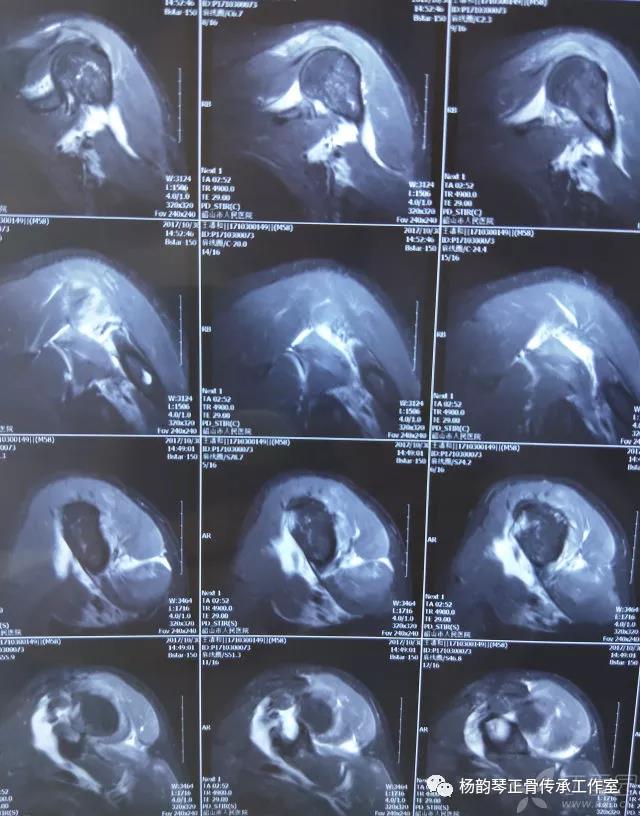

简要病史:骑摩托车跌倒致左肩部肿痛,活动受限,就诊于当地医院,拍片及磁共振检查后诊断为肩袖损伤及肩关节半脱位,予以悬吊固定,因症状缓解不明显就诊于我院。外院拍片情况如下:

磁共振检查也完善了,还是报了个肩关节半脱位……影像科已经把坑挖好了……